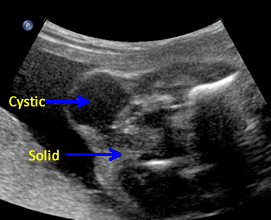

Above. Case 1. 24 3/7 weeks gestation. Sacrococcygeal teratoma. Longitudinal scan of lower spine showing sacrum with associated mixed cystic and solid mass.

Above. Case 1. 24 3/7 weeks gestation. Sacrococcygeal teratoma. An oblique scan through the same area shows both solid and cystic areas as well as calcifications, which are commonly seen in teratomas. The mass appeared completely external.

Above. Case 1. 24 3/7 weeks gestation. Sacrococcygeal teratoma. Similar part of the tumor as above showing cysts of various sizes.

Above. Case 1. 24 3/7 weeks gestation. Sacrococcygeal teratoma. The predominant cyst is large and contains anechoic fluid. No polyhydramnios or evidence for fetal hydrops were noted. Delivery occurred at term. Uneventful resection and repair occurred on day 2 of life.